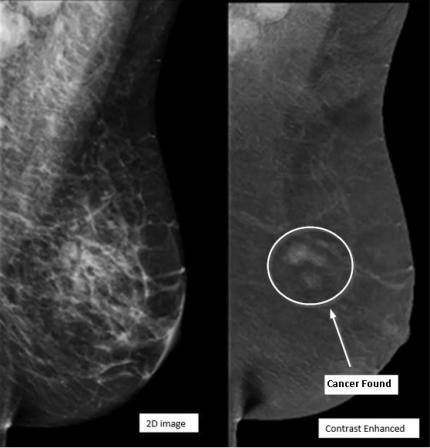

Contrast-Enhanced Mammography (CEM) provides exceptional clarity to find breast cancers that may not be visible in traditional mammography. CEM may be recommended by our breast radiologists as a supplemental cancer screening for elevated or high-risk patients (lifetime risk of breast malignancy greater than 15%) or to better assess the extent of malignancy prior to treatment. It can also be utilized as an alternative to breast MRI that delivers a fast, more cost-effective diagnosis.

Contrast-Enhanced Mammography is performed like a traditional mammogram with the addition of intravenous contrast - the same iodinated contrast that is used for a CT exam. Using IV contrast helps highlight areas of increased blood flow in the breast, which can be a sign of cancer. The CEM exam is performed in one of the mammography suites by a specially trained mammogram technologist and takes less than 10 minutes to complete. As contrast can affect renal function for patients over 60, diabetic patients, and some patients with hypertension, we will assess their renal function prior to scheduling. All patients will receive their CEM exam results before they leave our office.